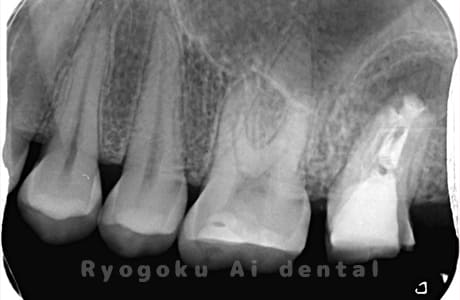

Case11

-

- 原因

- 左上4番歯根嚢胞

- 治療内容

- 歯根端切除法

- 治療費用

- ¥88,000

左上の歯を抜歯と宣告された、とのことでご来院された患者様です。歯根端切除術をマイクロスコープ下で行い、経過良好です。

<リスク・副作用>

外科手術のため、術後に出血、痛みや腫れ、違和感を伴います。口腔内の状態によっては適応できないことがあります。歯根端切除で治らなければ抜歯を検討しなくていけない場合もあります。